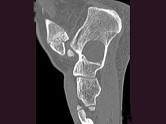

- 单项选择题男,32岁, 几天前踝部扭伤,疼痛, 不能行走,结合CT图像, 最可能的诊断是 ( )

A、骨囊肿

B、动脉瘤样骨囊肿

C、骨纤维异常增殖症

D、骨巨细胞瘤

E、畸形性骨炎